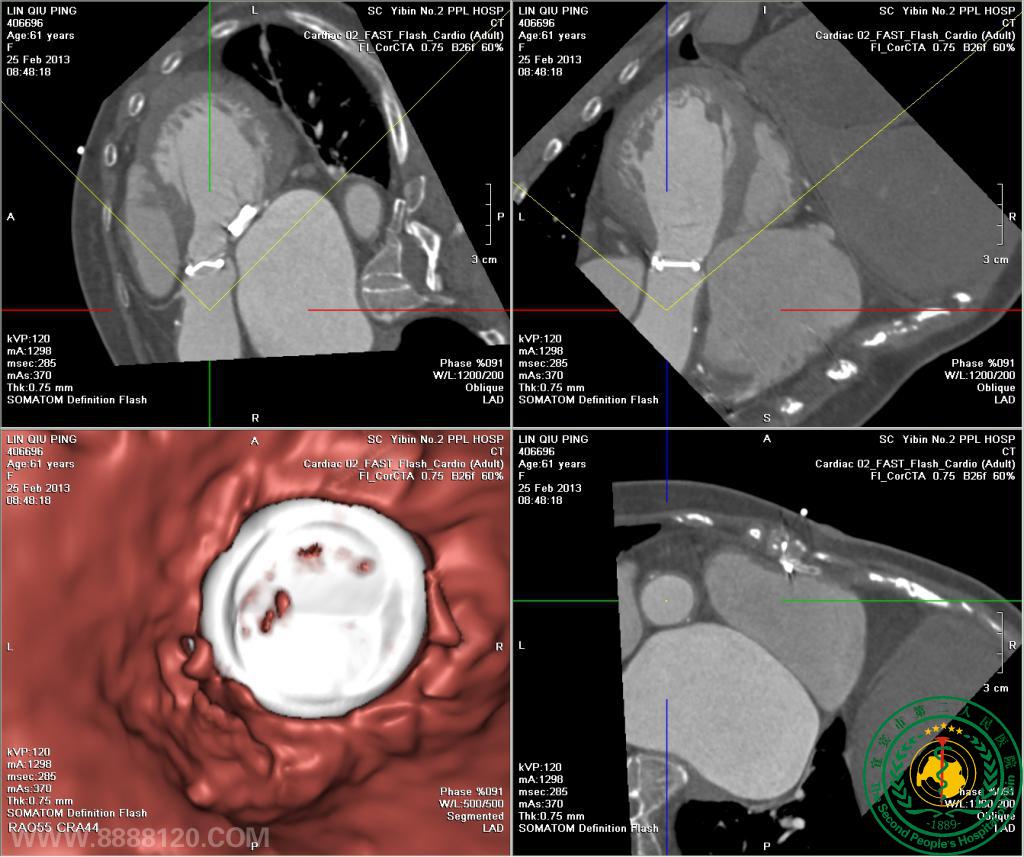

我院开展炫速双源CT对风心病的换瓣或成形术术前、术后评估技术

我院开展炫速双源CT对风心病的换瓣或成形术术前、术后评估技术3851